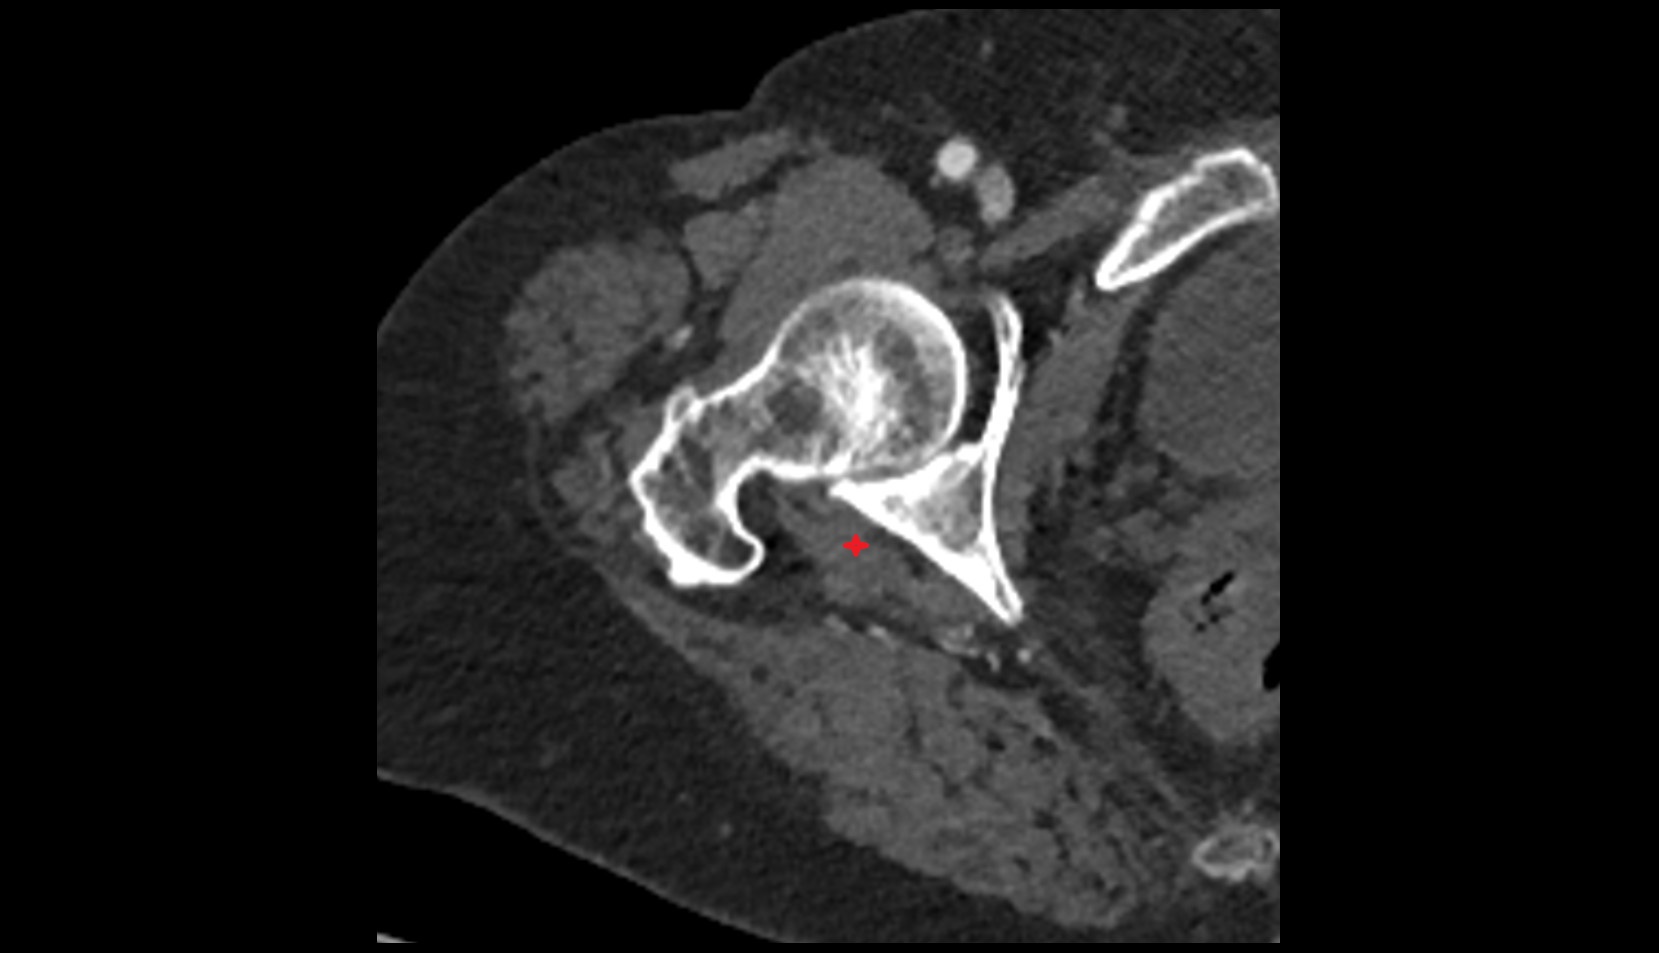

- Hip joint